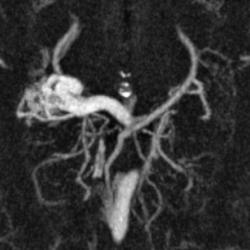

Предсталяю артериовенозную аневризму. Может кому-нибудь будет интересно.

Виден клубок неправильно развитых сосудов, питающихся от задней мозговой артерии и дренирующийся в прямой синус. Перифокальных изменений нет.

Черная стрелка - питащий сосуд - задняя мозговая артерия, зеленая - дренирующая вена к прямому синусу, красная - прямой синус.